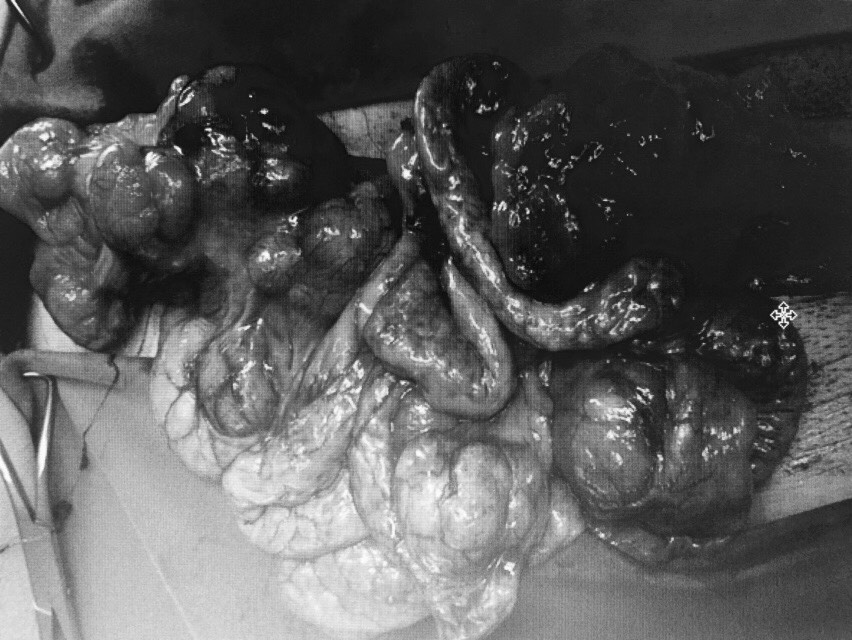

4. Những tình huống nguy hiểm khi nâng ngực có thể gặp?

TS Nguyễn Huy Thọ, Phó chủ tịch Hội phẫu thuật tạo hình và thẩm mỹ Hà Nội, cho biết trong quá trình phẫu thuật thẩm mỹ khách hàng có thể gặp phải các tình huống nguy hiểm như sốc phản vệ, chảy máu quá nhiều, nhiễm trùng, tái nhiễm trùng khi nâng ngực lần thứ hai. |